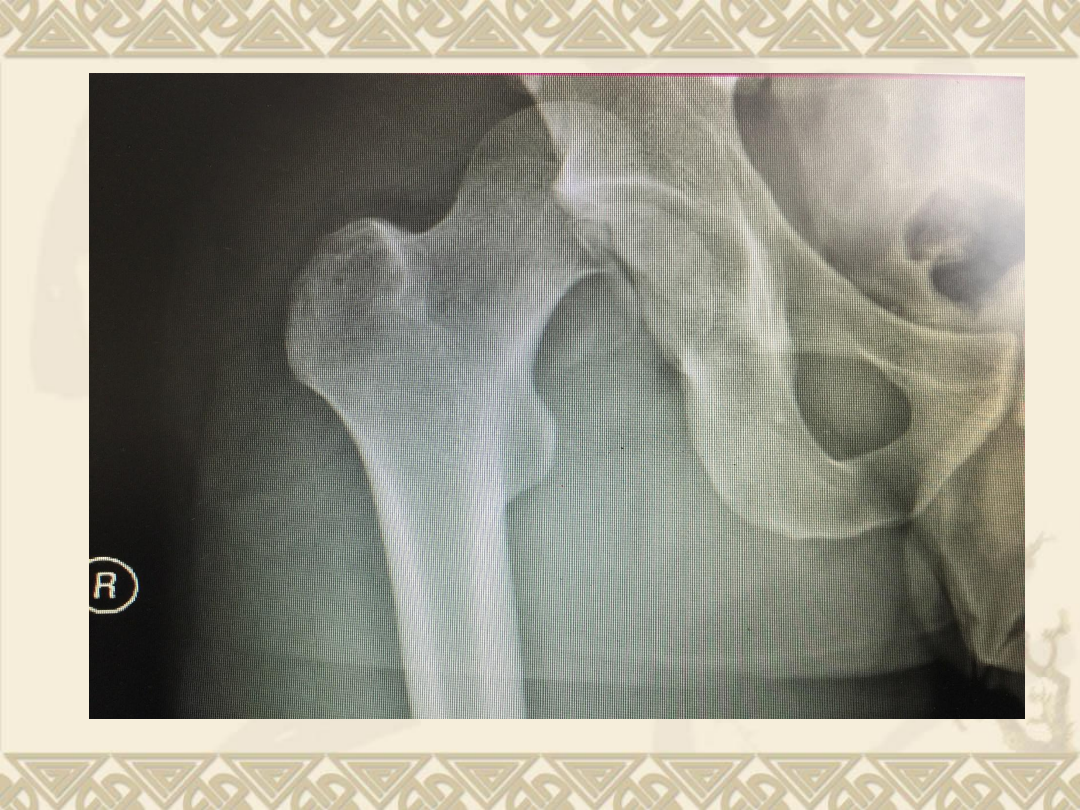

入院后拍片

v

1

、右股骨头骨折(

Pipkin

Ⅳ型骨折)

2

、髋关节后脱位

3

、髋臼后缘骨折